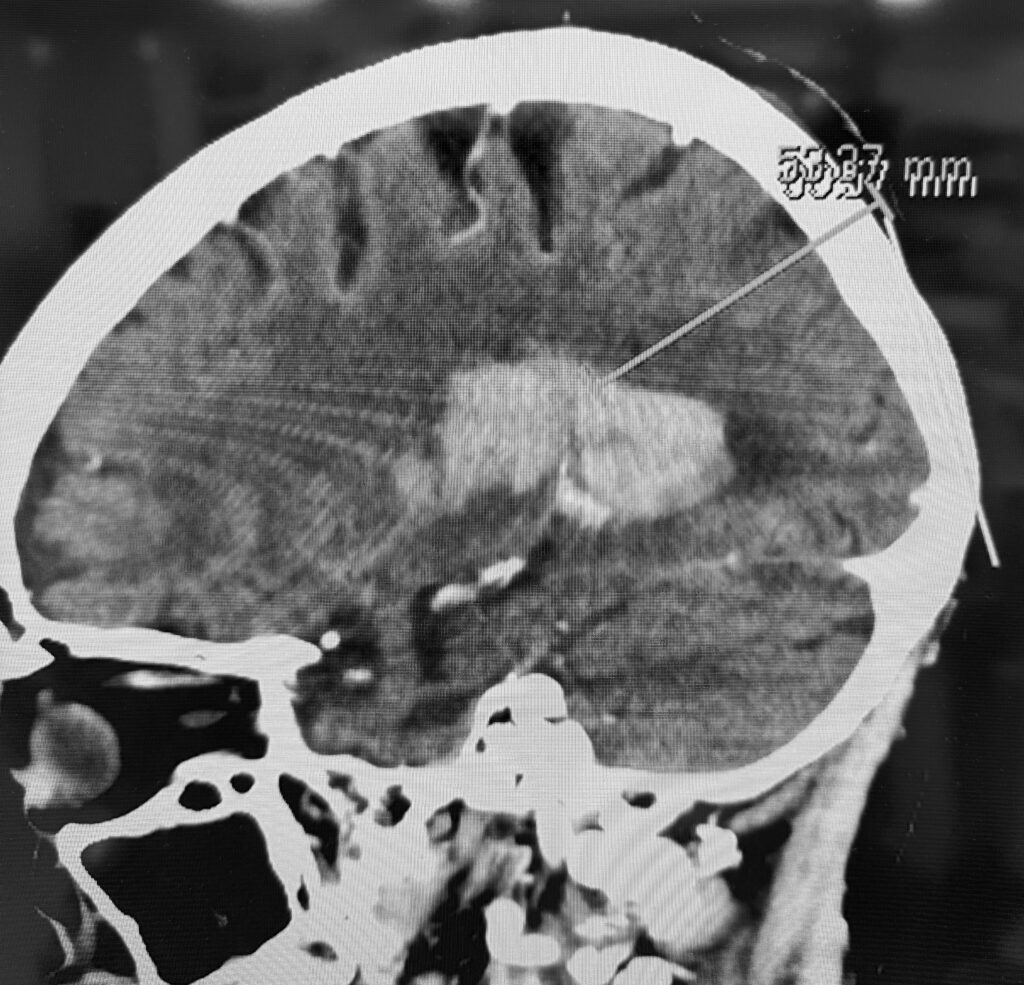

視床出血、脳室穿破の症例で、患者さんはご高齢なので内視鏡で低侵襲に血腫除去したいという要望でした。ご要望にお応えし、局所麻酔で3センチ切開し、1センチの穴を開けて血腫除去してきました。無事に血腫は取れたので今頃はリハビリテーションに励んでいることでしょう。

私は上記の写真のように個別にアプローチを決定し、透明シースを挿入し、内視鏡下に血腫除去する方法で良好な結果を得ています。ただし、エビデンスとなるとある程度の症例数を複数施設でまとめて、評価ポイントも決めて、別の治療方法との差を出して決まるので難しいです。